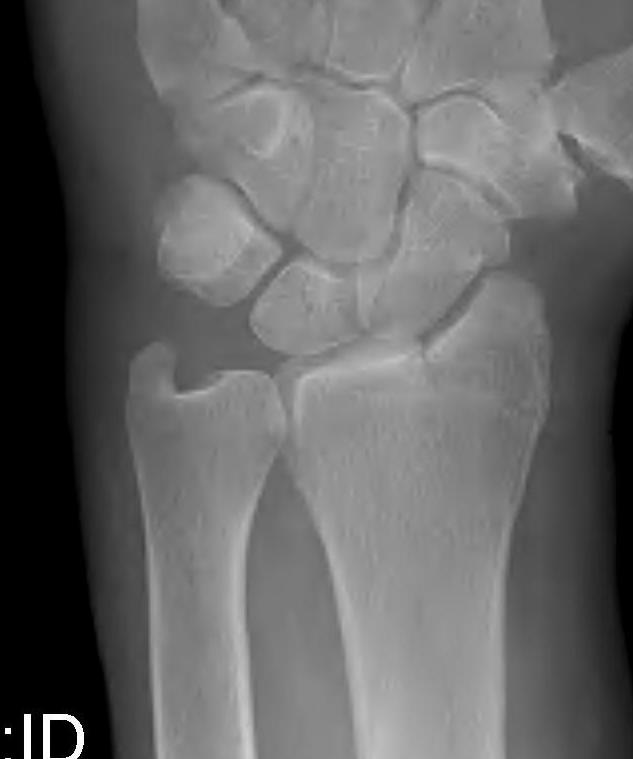

Distal Radius Angles

- radial volar tilt 11°

- radial inclination 22°

- radius is 11 mm longer than ulna

- ulna variance 2mm positive on average

Unacceptable reduction

1. Distal radial Step > 2mm

2. Articular incongruency sigmoid notch / DRUJ > 2 mm

3. Radial shortening > 5 mm

4. Radial inclination < 15o

5. Sagittal tilt

- > 15o dorsal

- > 20o volar